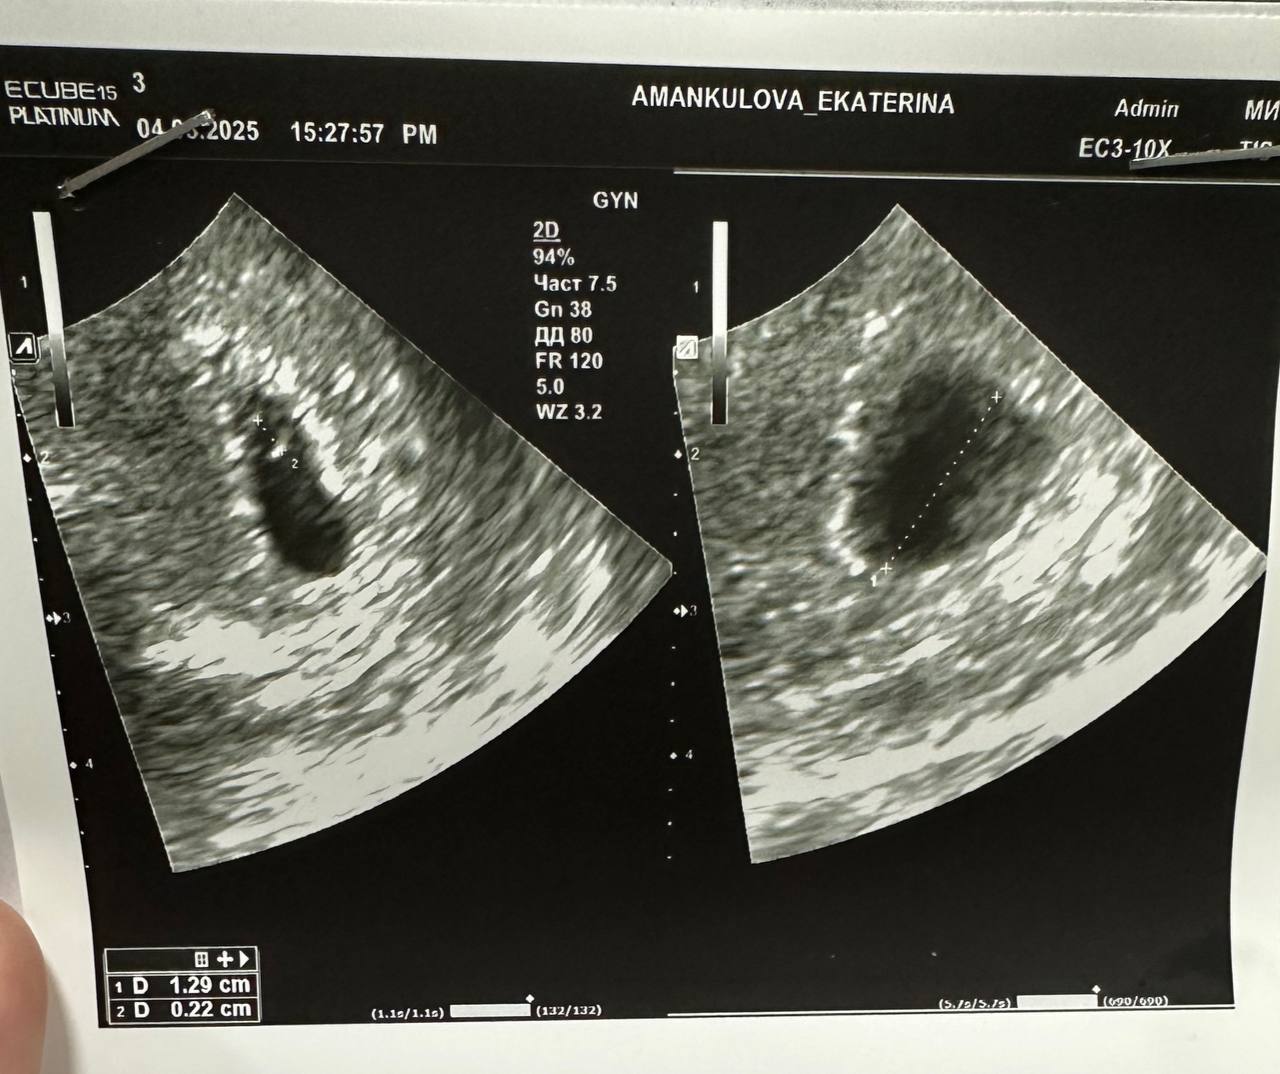

Девочки, кто опытный, подскажите пожалуйста. У меня ЖМ по узи 2,2мм это сколько недель? По узи поставили 4 недели, но так и не поняла это эмбриональный или акушерский? А когда измеряют КТР - то указывают срок эмбриональный или акушерский?

По ЖМ срок беременности не устанавливают. Смотрят по плодному яйцу. У вас диаметр ПЯ 12,9 мм, что соответствует 6 неделям и 1 дню.